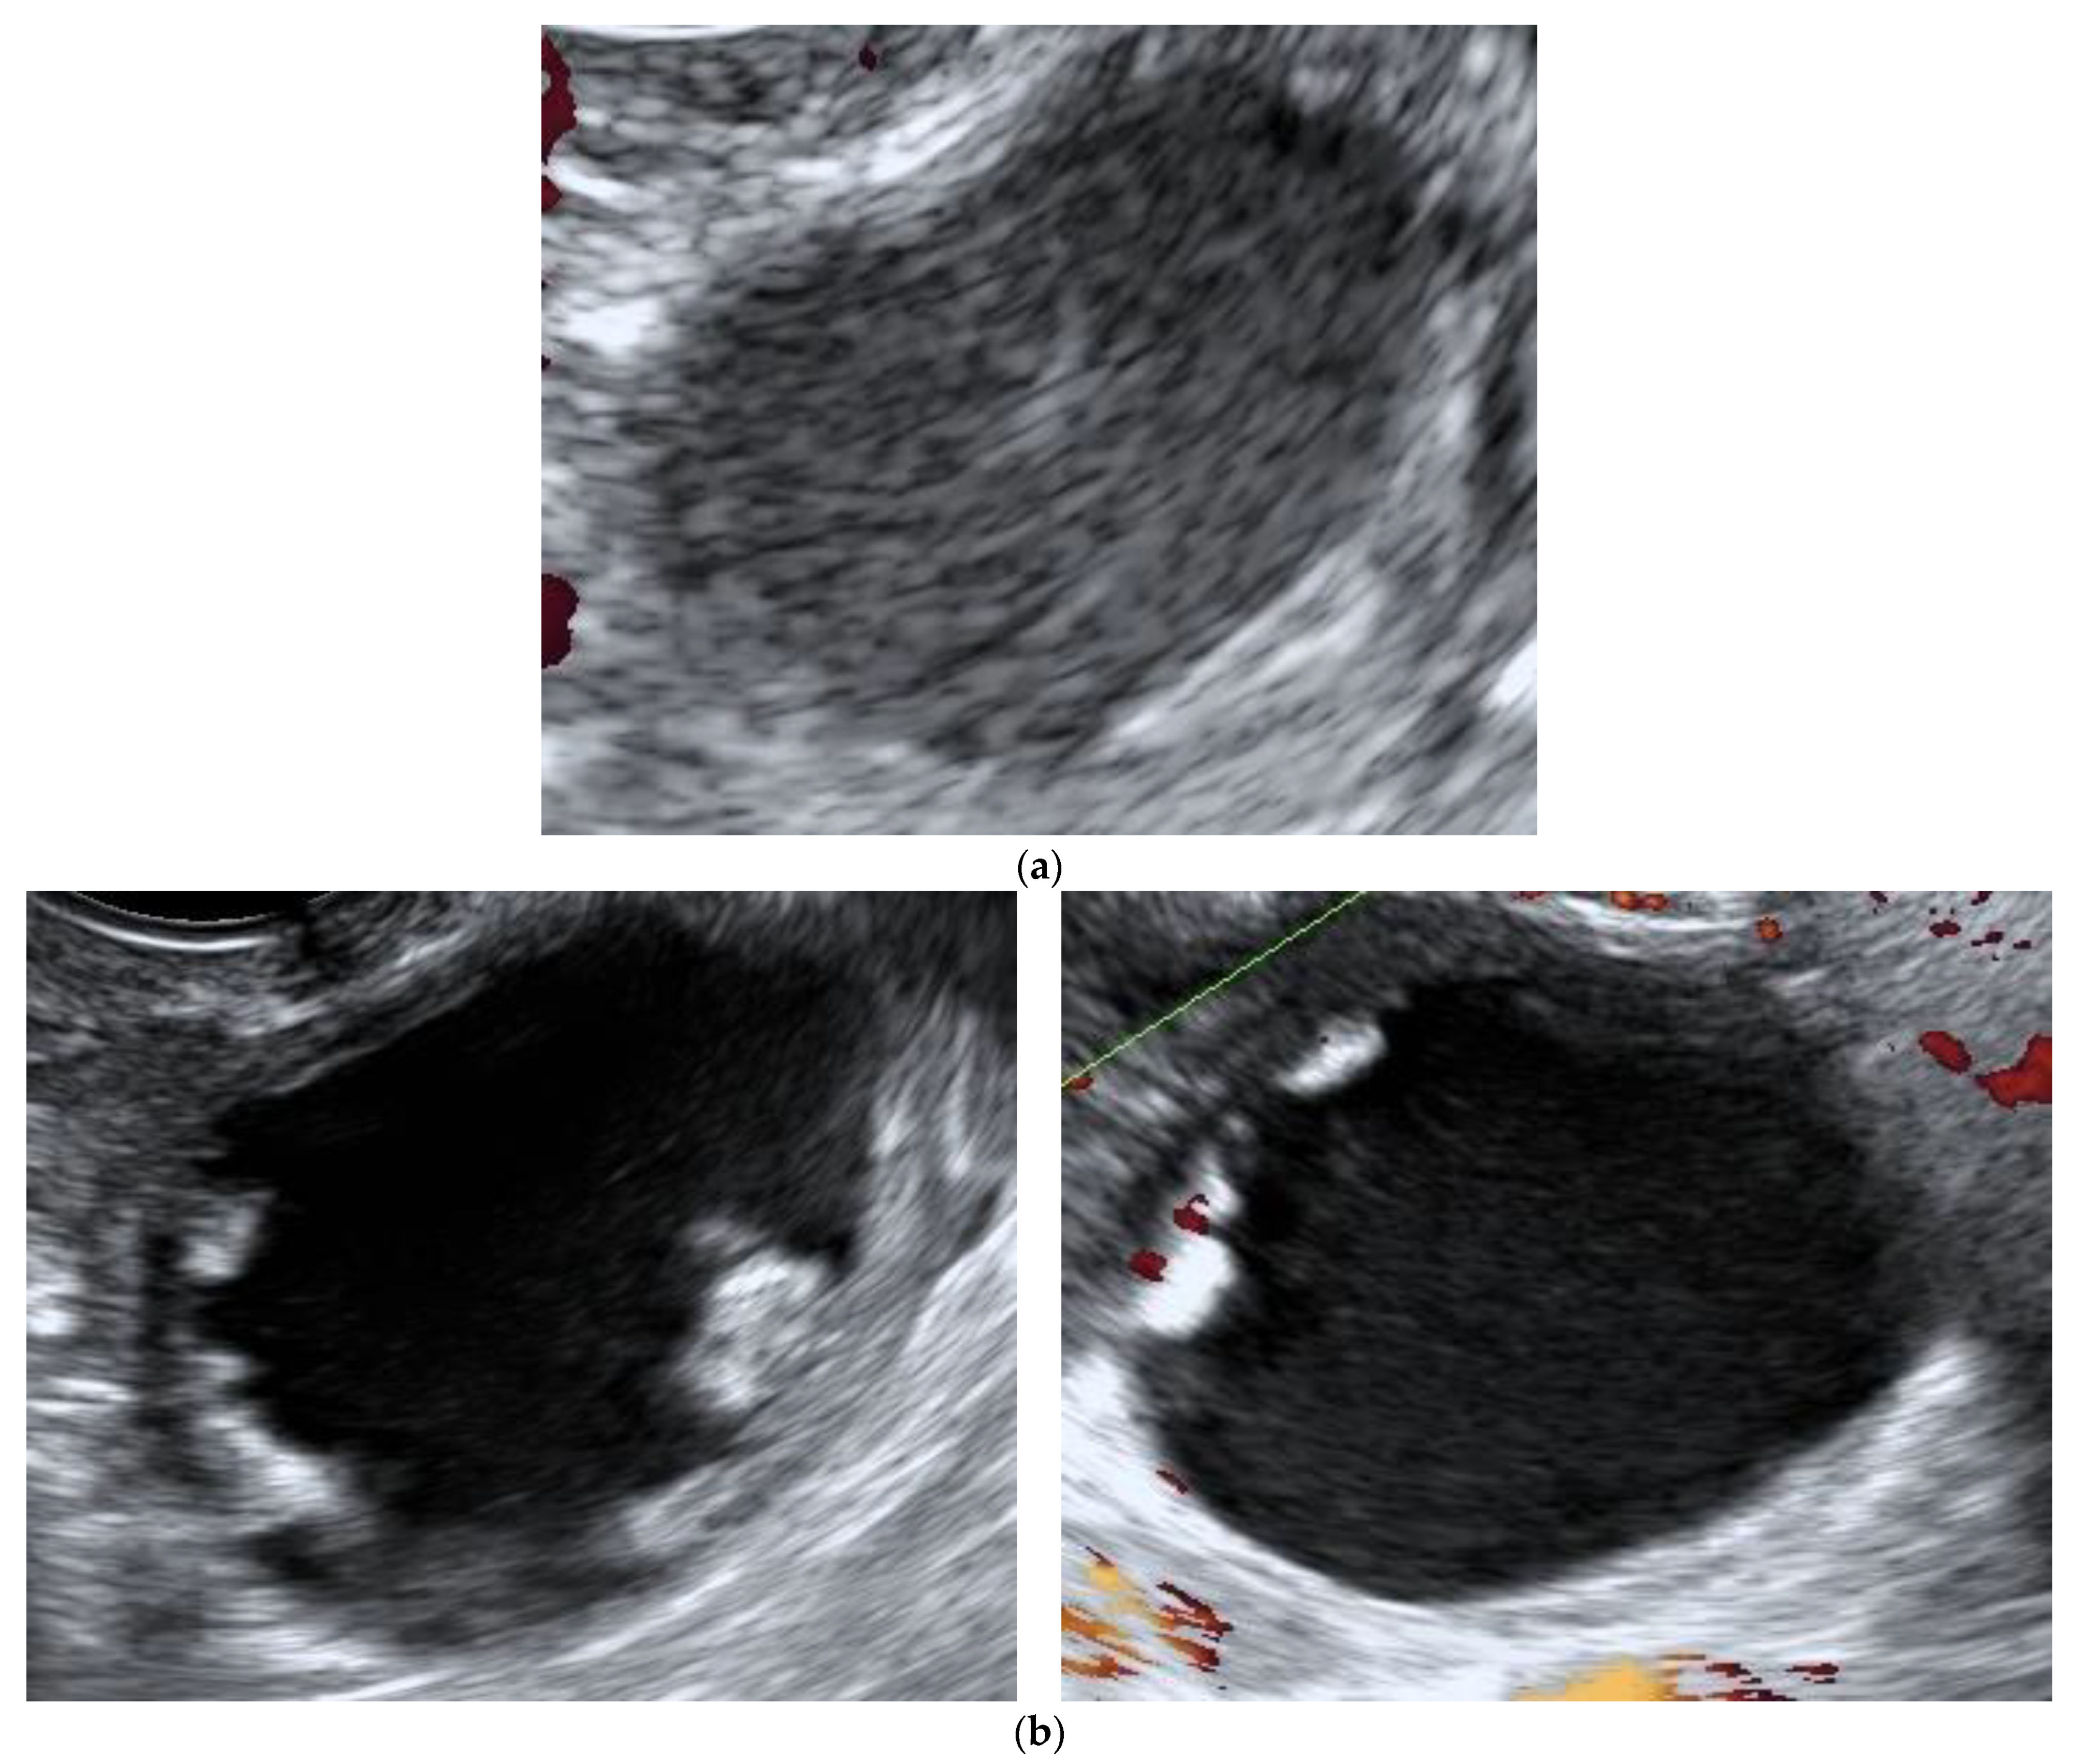

Figure 2.

Ultrasound features of borderline ovarian tumor initially classified as a benign lesion. (a) Unilocular ovarian formation with “ground glass” content and color score 1 with 35 × 30 × 20 mm, observed in an asymptomatic post-menopausal woman (age: 52 years), classified as a benign by the IOTA ADNEX model and assumed to be a sequel. (b) The same lesion with increased sonographic morphological complexity observed at the 3rd evaluation, 9 months after the diagnosis (multilocular—solid tumor with color score 3, CA-125 14.1 U/mL).